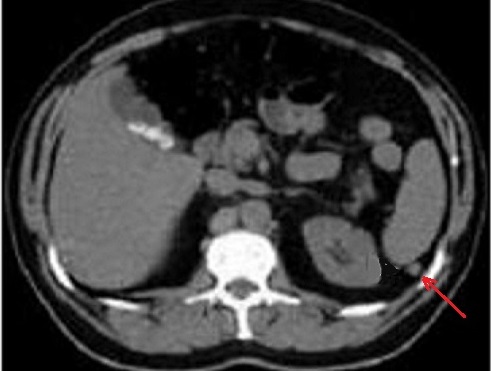

Image

radiologique TDM une rate surnuméraire à petite

taille situe au bord posterieure de la rate ( fléche

raouge ) . Aspect radiologique est une rate petite

homogène a bord nette , lisse , isodensité

retrosplenique |

Une autre cas de rate

surnumeraire avec la rate secondaire a petite taille

pre-splenique ( fléche rouge ) |